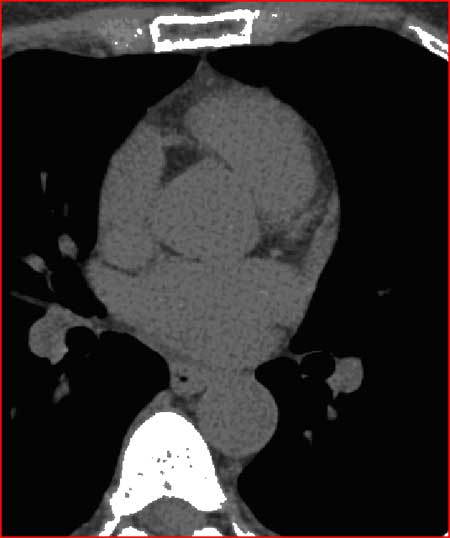

Heavily calcified coronary vessels with a score over 2000